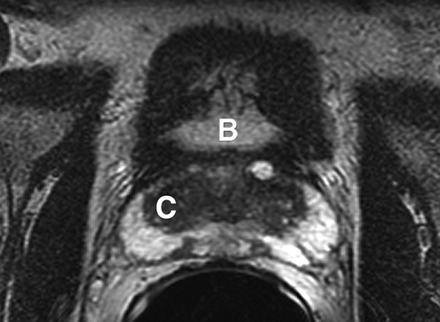

Most prostate cancers arise in the peripheral zone (PZ) [5], a region that may be compressed by the expanding transition zone (TZ) when there is significant BPH.

Although most prostate cancers originate in the PZ, up to 24% may arise in the transition zone (TZ) [5] and would therefore be missed by any biopsy protocol that sampled only the PZ.

Sextant biopsies were taken routinely ≈ 1 cm apart in the parasaggital plane bilaterally, at the base, mid-gland and apical regions of the prostate, as described by Hodge et al. [1]. In addition, six further biopsies were obtained, two from the TZ and four from the lateral PZ, as depicted in Fig. 1. The TZ biopsies were taken at the level of the mid-gland where the TZ was most prominent. The lateral PZ biopsies were taken by positioning the probe just medial to the lateral edge of the prostate at the base and mid-gland regions bilaterally, as described by Chang et al. [8]. This method generally allowed any area of DRE abnormality or suspicious hypoechoic lesion noted on TRUS to be incorporated into the biopsy protocol. All patients underwent the same biopsy strategy with no variance for gland size. Biopsies were obtained using an 18 G core-biopsy needle mounted on a spring-loaded automatic biopsy gun. All patients were placed in the left lateral decubitus ('knee-chest') position and all were examined with no prior bowel preparation. The procedure was generally well tolerated and no patient required intravenous sedation or narcotic analgesia. All TRUS was undertaken by the same operators (D.R.G. and N.S.), either personally, or when supervising a higher urological trainee.